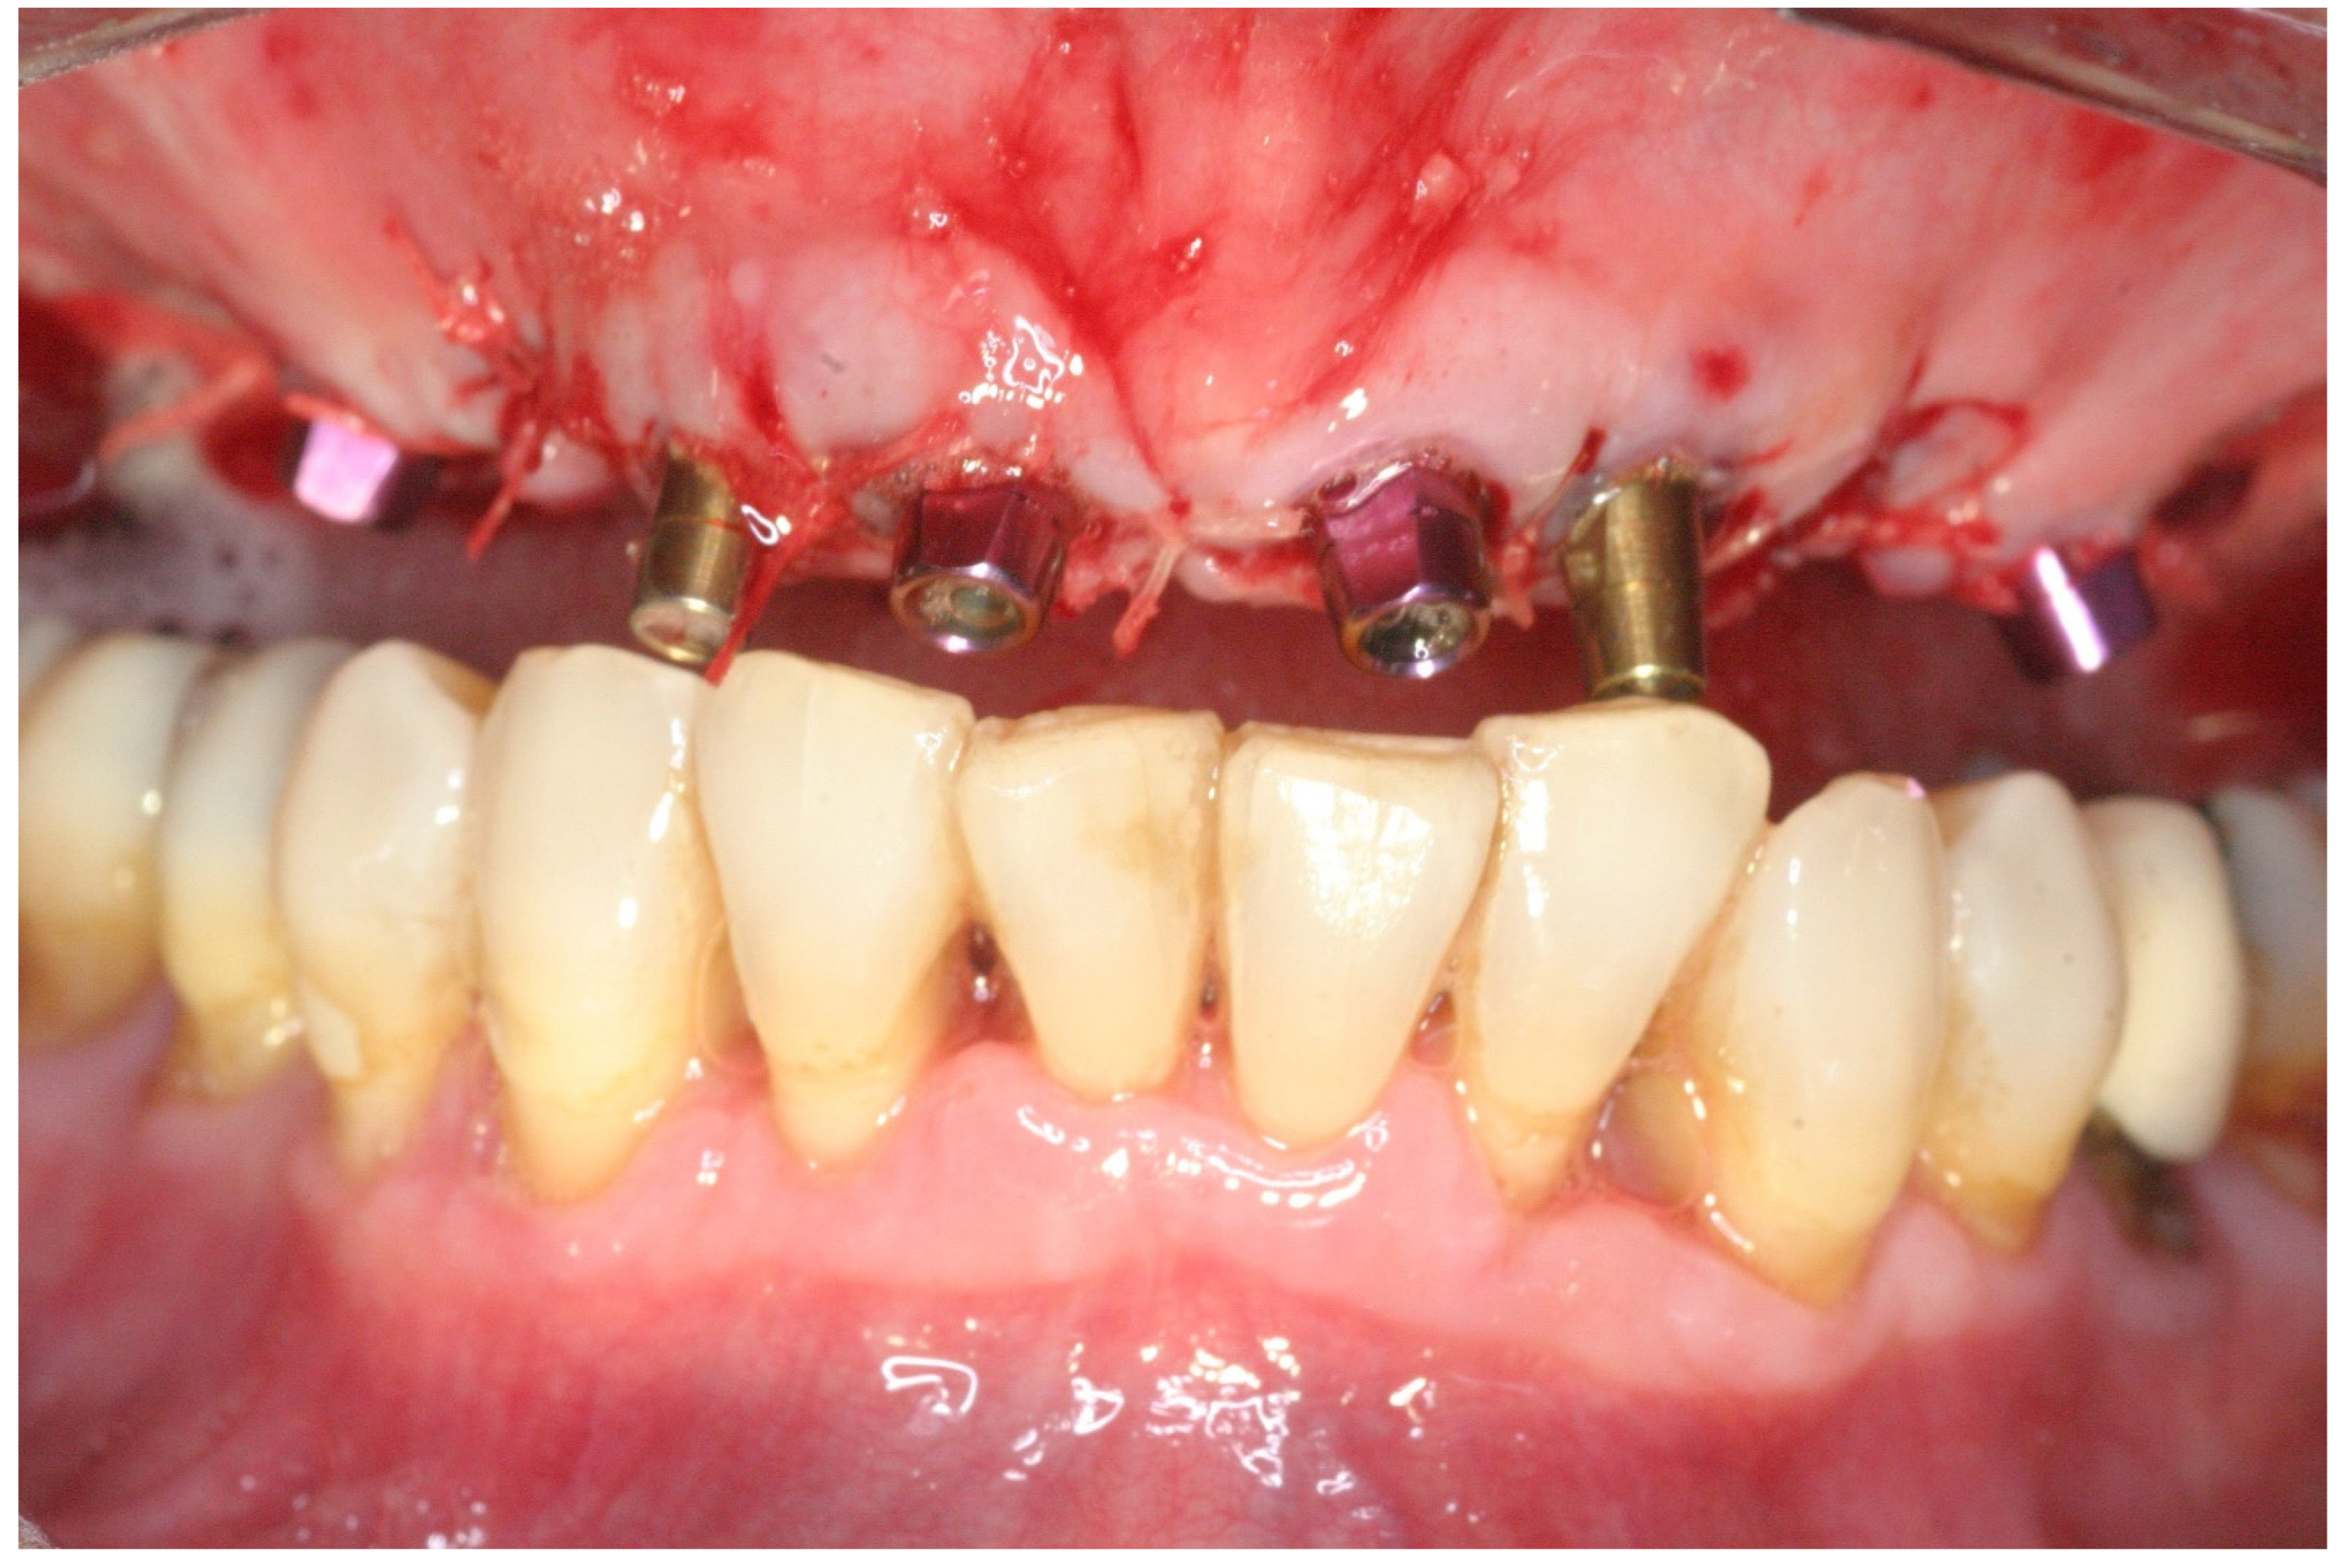

2.2. Surgical Treatment